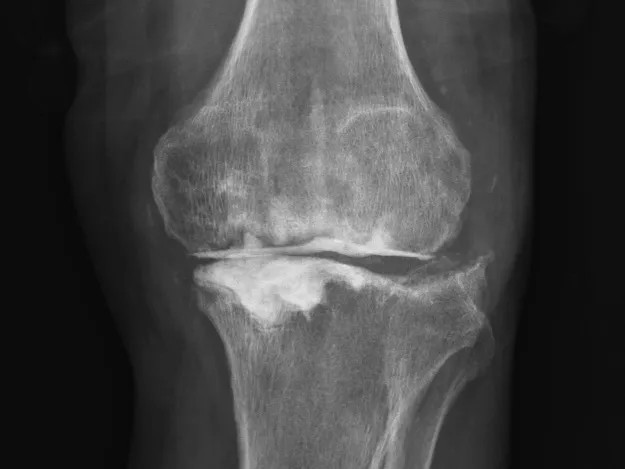

68歲的張先生(化名),本以為一次膝關(guān)節(jié)單髁置換手術(shù)能終結(jié)他的疼痛。然而,術(shù)后感染不期而至,將他的生活拖入長達(dá)8個(gè)月的灰暗期。

膝關(guān)節(jié)持續(xù)紅腫、疼痛,每一步都伴隨著不適與恐懼。反復(fù)治療,效果卻不盡如人意。傳統(tǒng)手段面對(duì)此類術(shù)后感染、結(jié)構(gòu)遭破壞的復(fù)雜局面,往往力不從心,患者可能需要經(jīng)歷多次手術(shù),且功能恢復(fù)難以保障。

清創(chuàng)只是第一步,如何在一片“復(fù)雜地形”中重建一個(gè)穩(wěn)定、功能良好的膝關(guān)節(jié),是更大的挑戰(zhàn)。為此,團(tuán)隊(duì)引入了計(jì)算機(jī)輔助手術(shù)規(guī)劃系統(tǒng)。

通過患者的CT數(shù)據(jù),系統(tǒng)構(gòu)建出膝關(guān)節(jié)的三維數(shù)字模型,精確評(píng)估骨缺損的范圍與形態(tài)。醫(yī)生可以在虛擬空間中,提前模擬手術(shù)過程,為患者“量體裁衣”,規(guī)劃出假體安放的最佳位置、角度以及所需填充骨缺損的特殊墊塊型號(hào)。